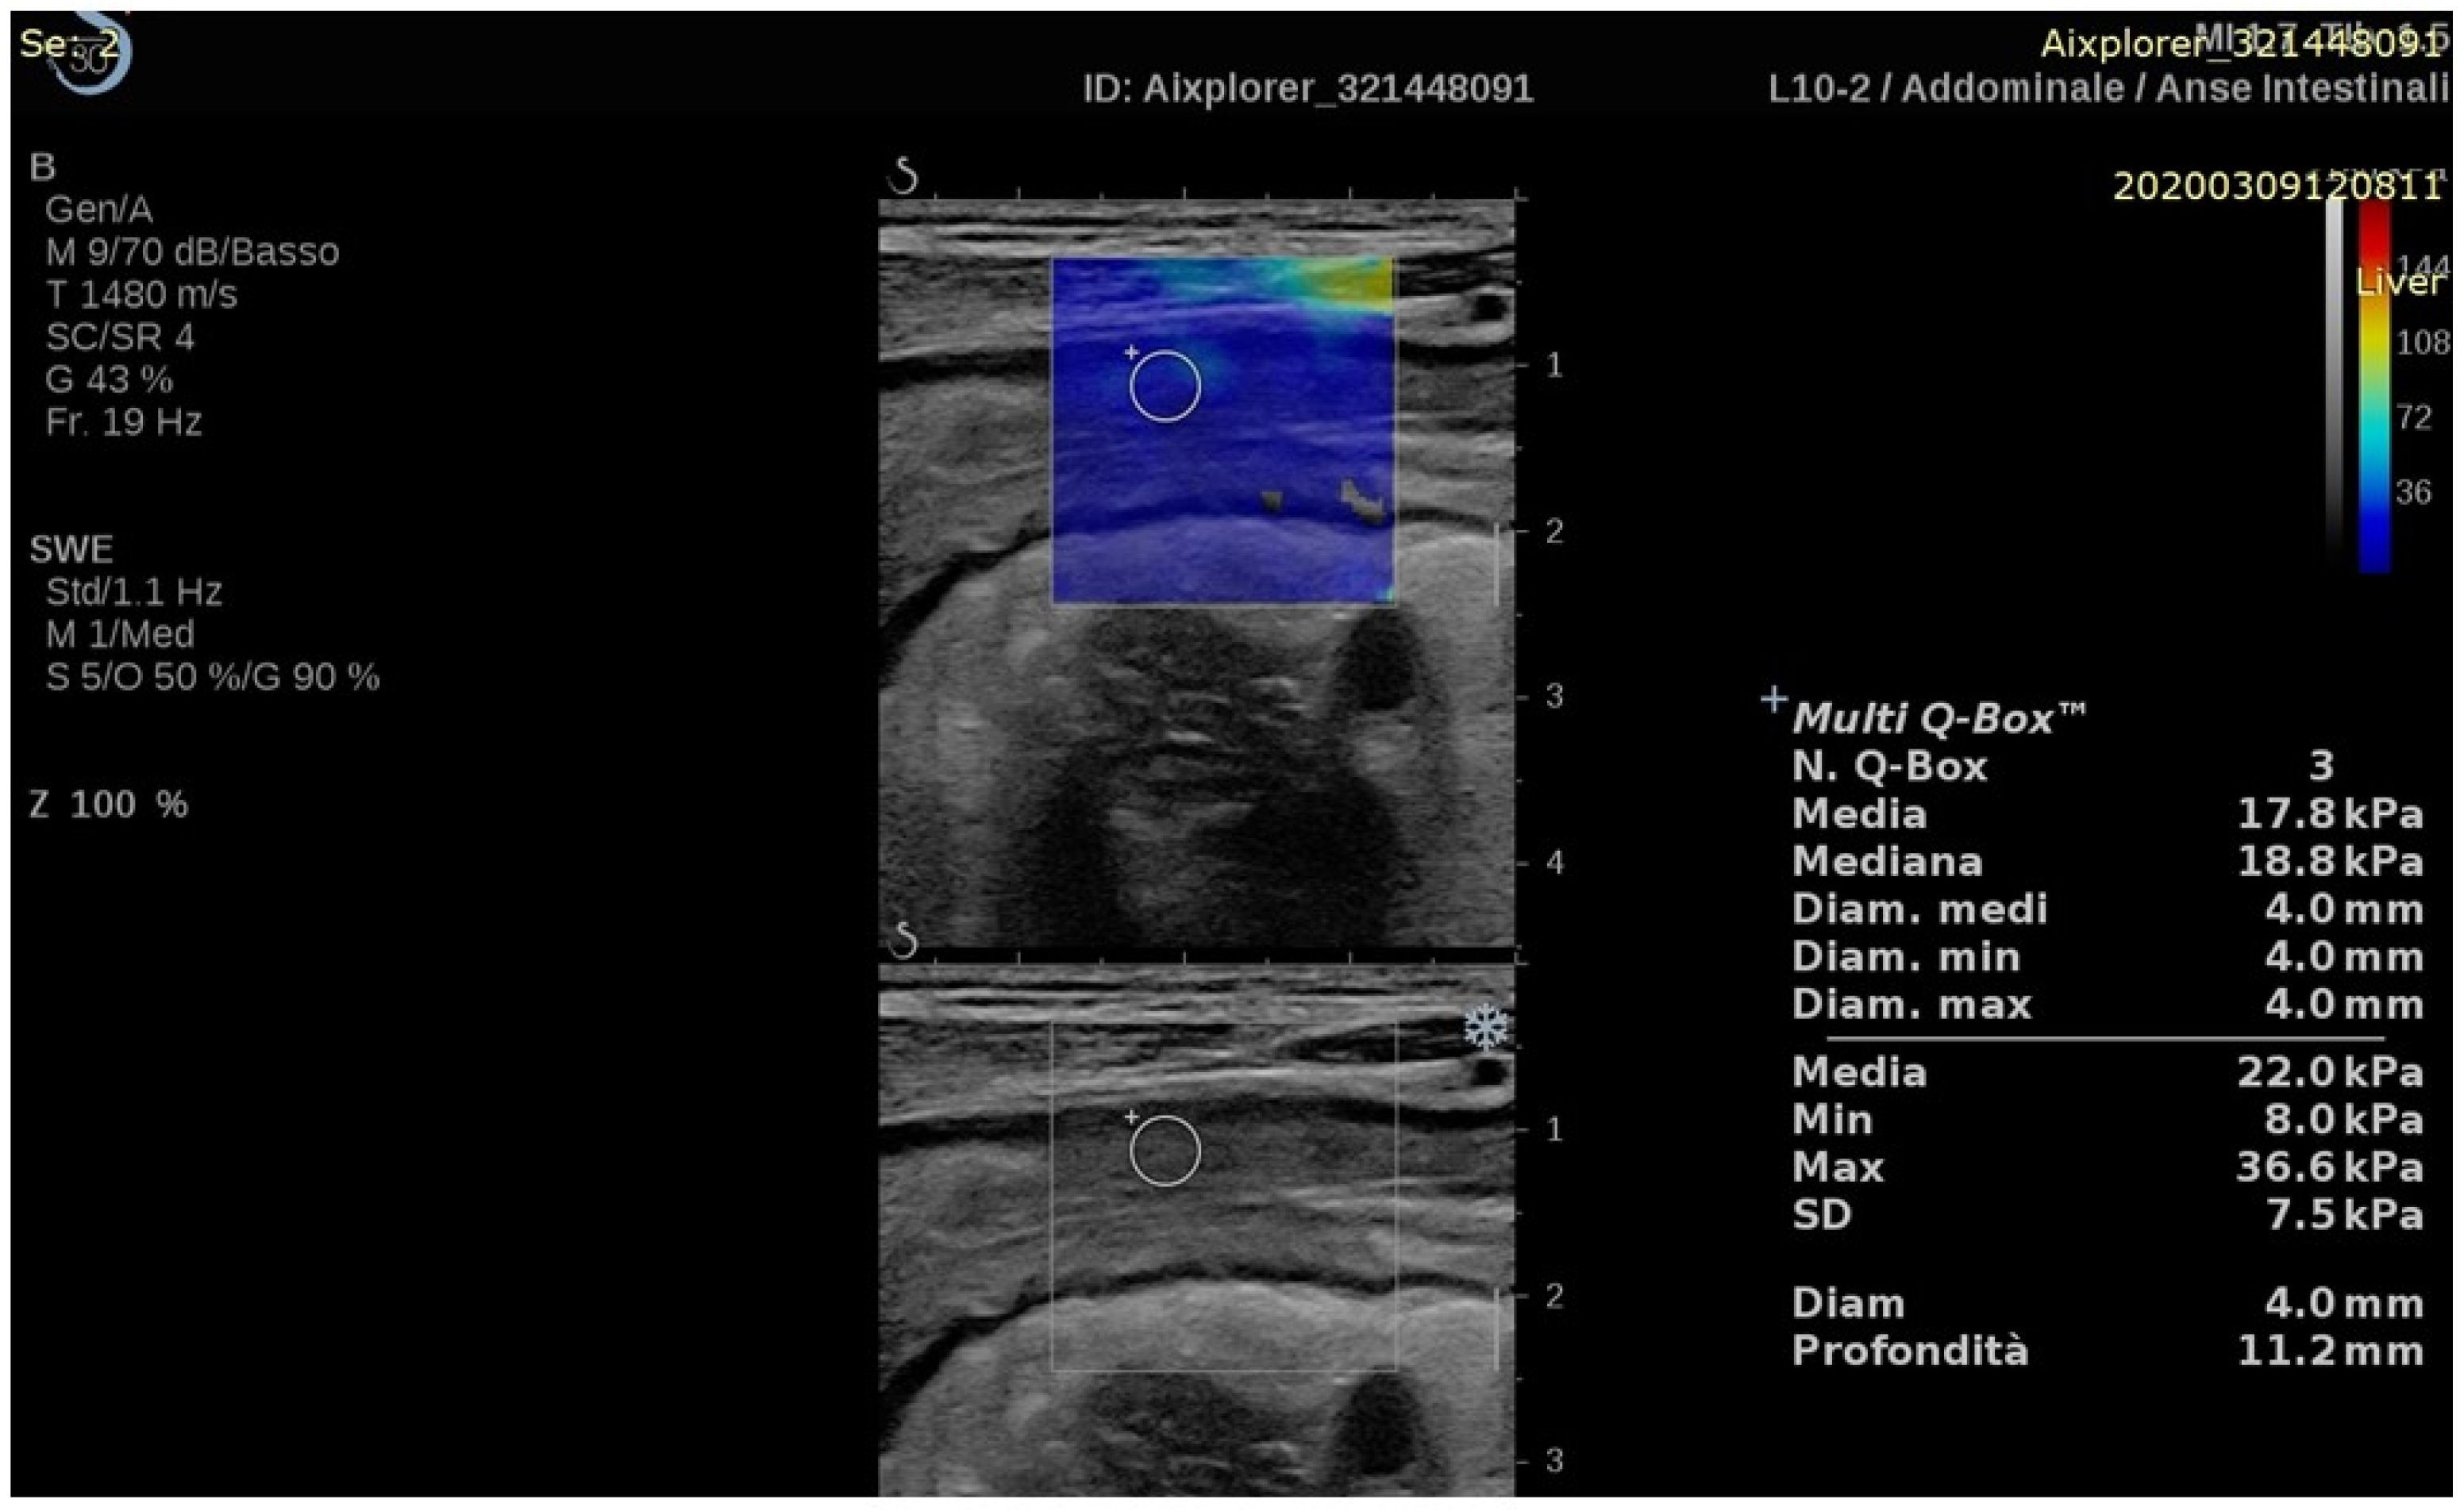

| Chen (2018) [29] | CD | Stricture characterization | Prospective (35) | Aixplorer, SuperSonic Imagine | 2D-SWE | 2D-SWE values were higher in severe fibrosis compared to mild or moderate fibrosis (23.0 ± 6.3 vs. 17.4 ± 3.8 and 14.4 ± 2.1 kPa, p = 0.008). | Histology |